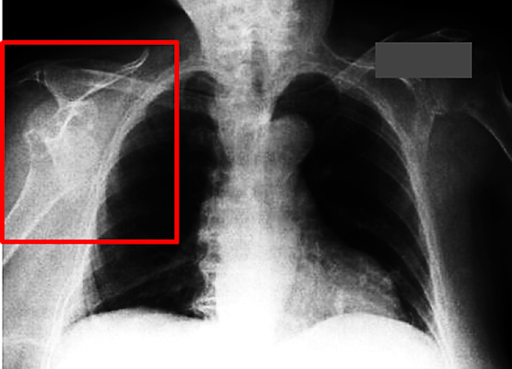

Figure 1: Radiological Example

Figure 1. Chest X-ray demonstrating right anterior glenohumeral dislocation. The humeral head is displaced inferiorly and medially, no longer articulating with the glenoid fossa.

Though chest radiographs are suboptimal for dedicated shoulder evaluation, certain key findings can reveal dislocation:

• Loss of articulation between the humeral head and the glenoid

• Medial and inferior displacement of the humeral head relative to the glenoid

• Empty glenoid sign

• A coexisting fracture may sometimes be visible (e.g., greater tuberosity)

These features are readily appreciated in Figure 1 and Figure 2, indicating anterior glenohumeral dislocation.